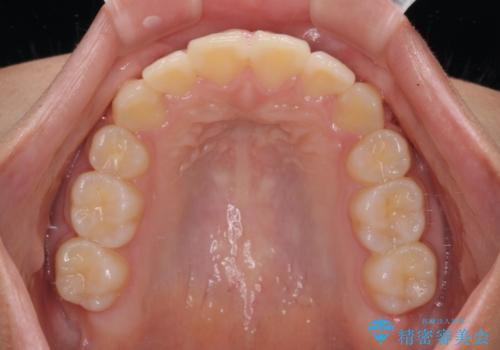

急速拡大後、歯列はきれいに並んだのですが、口元が出っ歯になってしまったため、速やかに抜歯を行い、治療期間がいたずらに遅延することのないようにしました。

- 歯列全体の叢生を気にして来院された患者様です。

検査を行った結果、上顎骨の横幅が相対的に狭いことが分かり、叢生が強いことから、急速拡大装置にて上顎骨を側方に拡大することで、叢生の解消と奥歯の咬み合わせ改善を図ることとしました。